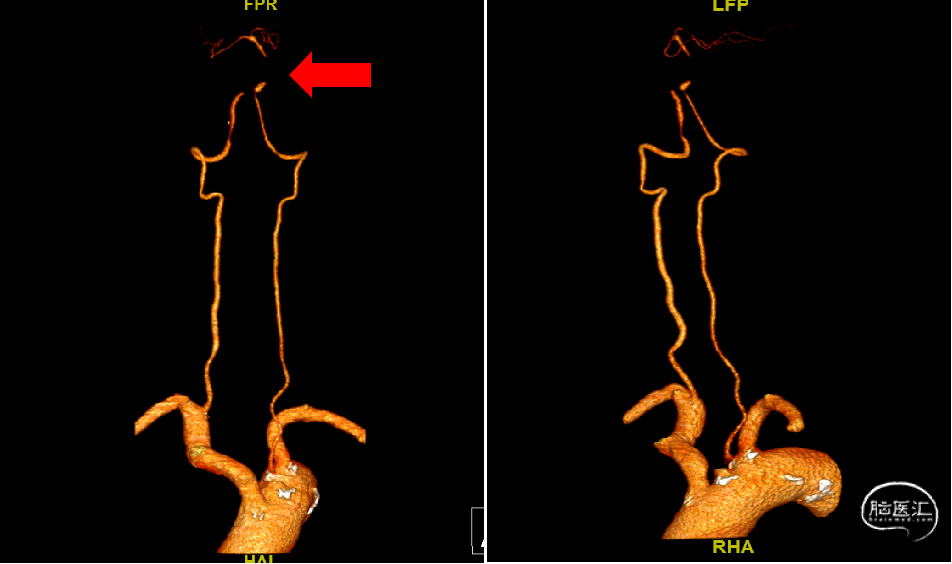

CTA评估:基底动脉闭塞;右侧椎动脉优势;左侧椎动脉纤细,起至主动脉弓。术前评估入路:经右侧椎动脉途径取栓。

术前基底动脉CTA